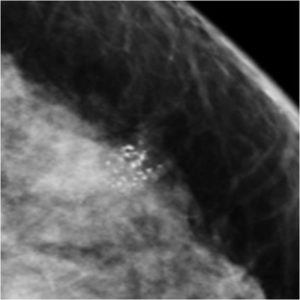

59 Yr old female, referred from outside for suspicious microcalcifications in left breast.